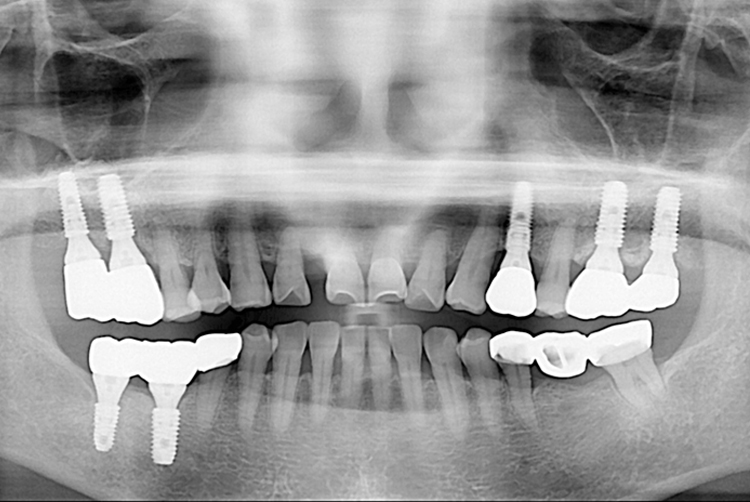

[임플란트] 임플란트

5a52b2f167618046e479c86ed9a68b9b.jpg

치료전 : 2019-04-10

세종치과는 많은 환자와 다양한 케이스를 바탕으로 항상 편안한 임플란트 수술을 제공하고자 노력하고,

오래동안 튼튼히 쓸 수 있는 임플란트 수술을 가장 큰 목표로 삼고 있습니다